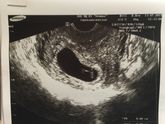

Была сегодня на узи, срок 6 недель и 6 дней ( завтра 7 неделек будет ?)

Плодное яйцо уже 2,4см ( а 1,5 недели назад было всего 6 мм ), КТР 8 мм ( наша креветочка ?), сердцебиение 136 уд/м, есть небольшой тонус, также загиб матки ,а так всё хорошо . Теперь … Читать далее

Была на УЗИ, беременность подтвердили 5 недель, плодное яйцо 6мм ( есть небольшой загиб матки )?❤️? счастью нет предела ?? в общем все хорошо, наш крошик растёт .Следующее узи через 2 недели ( узи делала на 6 день задержки, цикл 28)